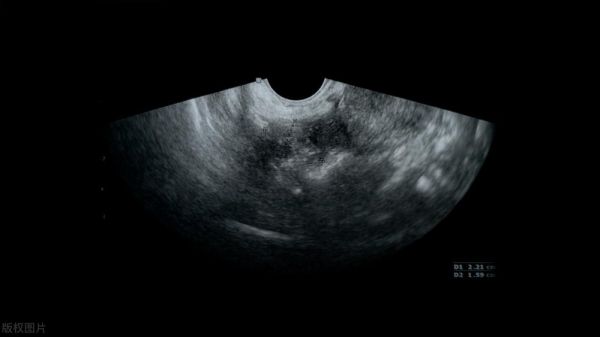

B超:回声原理成像

B超不是用射线,而是用超声波来观察身体内部结构。其原理是用超声波穿透人体,当声波遇到不同的组织,特别是组织界面时会产生反射波,超声探头一面发出超声,一面接受反射波,并通过计算反射波成像。就像挑西瓜一样,边敲打边通过反射回来的声音推测西瓜熟了还是不熟。

5腹部/盆腔——除肠道外,超声是初筛首选检查

腹腔器官实质脏器都是软组织密度,X线难以显示病变。而超声波检查对肝脏、脾脏、胰腺、肾脏、盆腔脏器等疾病诊断准确率较高,所以首选超声波检查进行初步诊断。CT、核磁往往是在超声波检查初步诊断后进一步鉴别的手段。 超声波检查受气体干扰很大,对于肠道等含气较多的器官,诊断准确率会降低,因此胃肠道检查常选择使用钡餐造影检查或胃肠镜检查。

优点:多方向观察,实时成像缺点:检查时间较长,对宠医技术要求较高;需要对宠物剃毛;同时超声受气体干扰较大,对于含气较多的器官,诊断准确率会降低。

B超主要项目:判断患处有无肿物、异物、炎症、积液、钙化、纤维化、气体等DR主要项目:骨折类、肺脏病气管炎类、异物吞食类、宠物孕晚期检查类等DR和B超对于宠物诊断是互补的,很多宠物就诊费用贵,也是因为需要多项检查才能更好的确诊治疗。